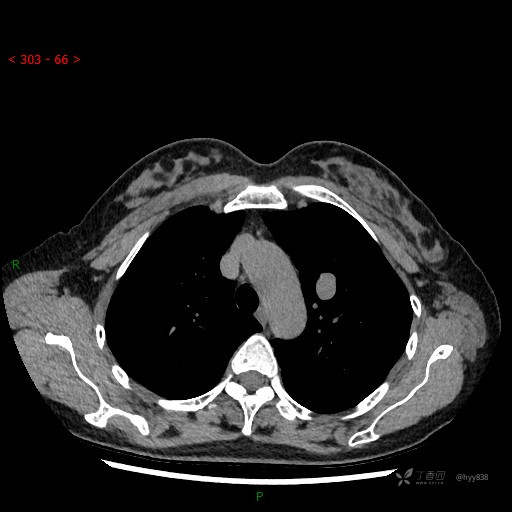

胸部CT平扫